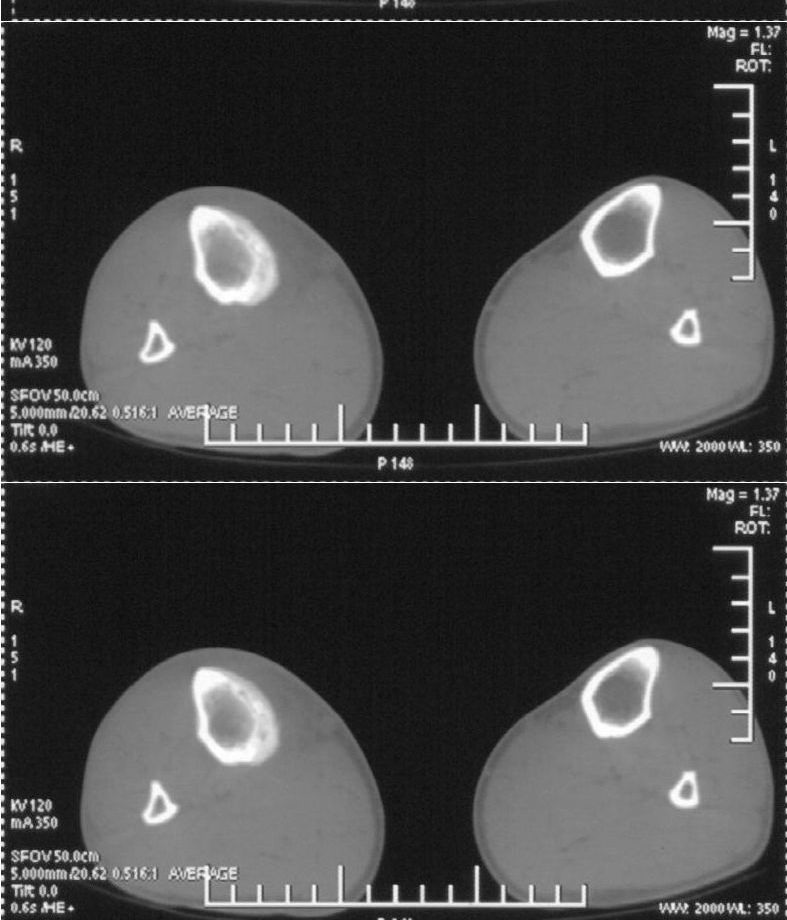

男,42岁。4个月前钢筋钝伤右侧小腿部,当时因无明显外伤,未引起重视。一周后因受伤腿部疼痛,发现肿胀,随后到当地医院进行检查(2008年4月16日)。因未发现骨质异常未引起重视,仅仅进行口服抗生素治疗处理。经过一段时间治疗但未见明显治疗效果在5月29日又进行x线检查,发现有胫骨密度上段密度增高,又进行抗炎治疗,仍未见效果。又在7月3日进行x线检查,仍然报告有胫骨上端密度增高,并建议ct检查。以下是相关检查结果:

该患者到某三级医院进行会诊,并重新作了平片检查,认为畸形性行骨炎:

髓腔密度呈絮状增高,胫骨上端内侧可见层状骨膜反应,考虑骨髓炎.

髓腔密度呈絮状增高,胫骨上端内侧可见层状骨膜反应,肌间隙模糊,考虑骨髓炎.